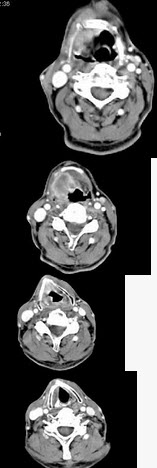

男,63岁,咽喉部不适约一年,近2个月经常咳嗽,痰中带有血丝,CT如图所示,应诊断为()

A、梨状窝癌

B、声门型喉癌

C、声门下型喉癌

D、声门上型喉癌

E、混合型喉癌

D